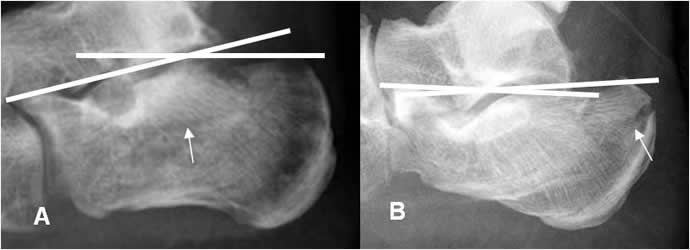

Angulo de Böhler:

Se mide con una proyección lateral de Rx. Está formado por la intersección entre las líneas que unen la parte mas superior del calcáneo, con su parte anterior y posterior. La amplitud normal está entre 20º y 40º. En casos de fracturas, el ángulo está disminuido. (Fig 90 y 91).

Fig 90. Angulo de böhler.

Rx lateral. Angulo normal.

Fig 91. Fractura del calcáneo.

A y B: Rx lateral. Fracturas impactadas del calcáneo. En A hay disminución del ángulo de böhler y en B, inversión.